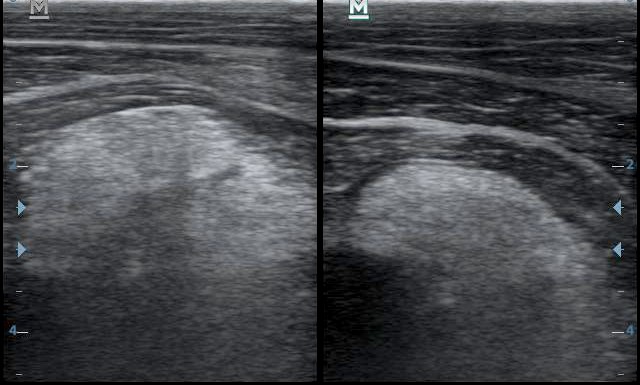

A két felvételen a két biceps ín keresztmetszete látható. A bal oldali, sérült ín erősen megnagyobbodott, szabályos, fehér, „pöttyös” szerkezete felbomlott. A jobb oldali ín normális.